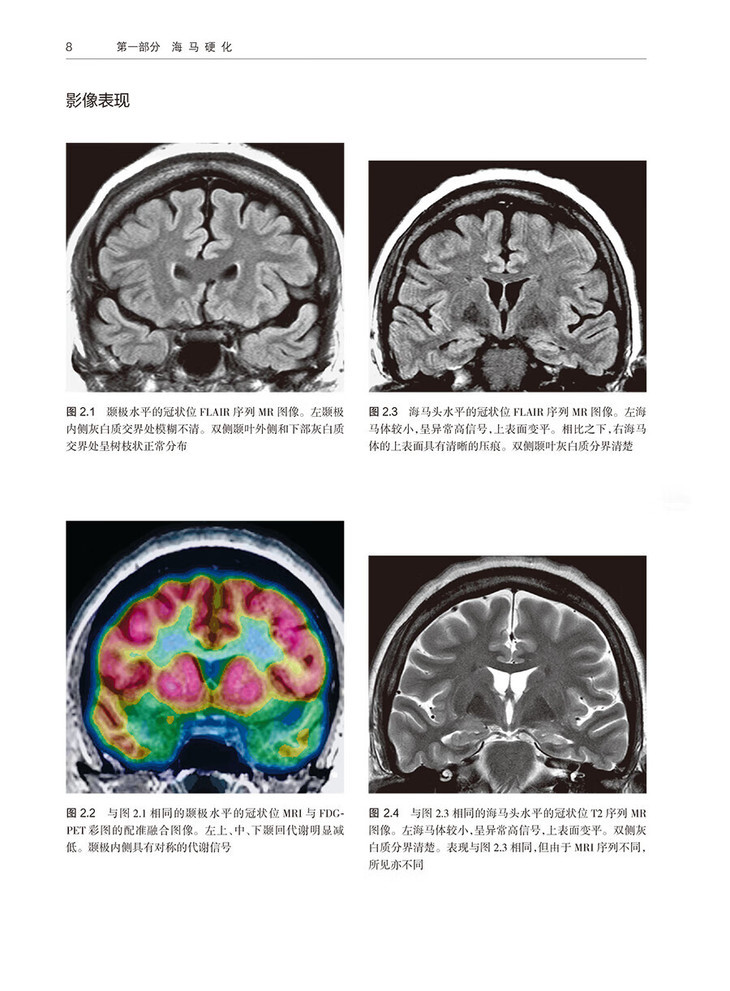

2 中度单侧海马硬化 /7